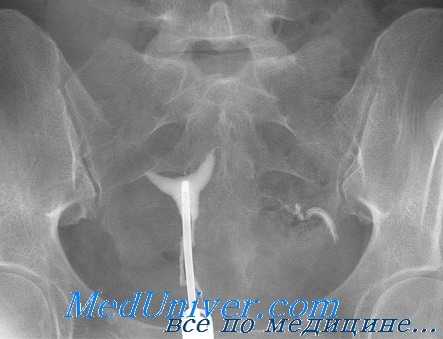

Серологические исследования на хламидии также могут сыграть свою роль при обследовании бесплодной пары. К примеру, если результаты первичного обследования, включающего ГСГ, оказались в пределах нормы, традиционно следующим шагом становится лапароскопия. Однако остается неясным, стоит ли применять лапароскопию в том случае, если у пациентки не было ЗППП или хронических болей, так как нет точной уверенности, что вероятность обнаружения какого-либо заболевания перевесит риск самой процедуры. В такой ситуации принять решение поможет анализ на антитела к хламидиям.

Некоторые специалисты в области лечения бесплодия предложили методику изучения патологии маточных труб, начинающуюся с серологического анализа на хламидии. Если результат отрицательный, считают они, то в дальнейшей ГСГ нет необходимости. Если же серьезные подозрения вызывает наличие в анамнезе пациентки перенесенных инфекционных заболеваний или серологический анализ дал значительные показатели, для дальнейшего исследования можно применить ГСГ или лапароскопию. Последний метод позволит получить патогенные микроорганизмы из маточных труб или Дагласова кармана.